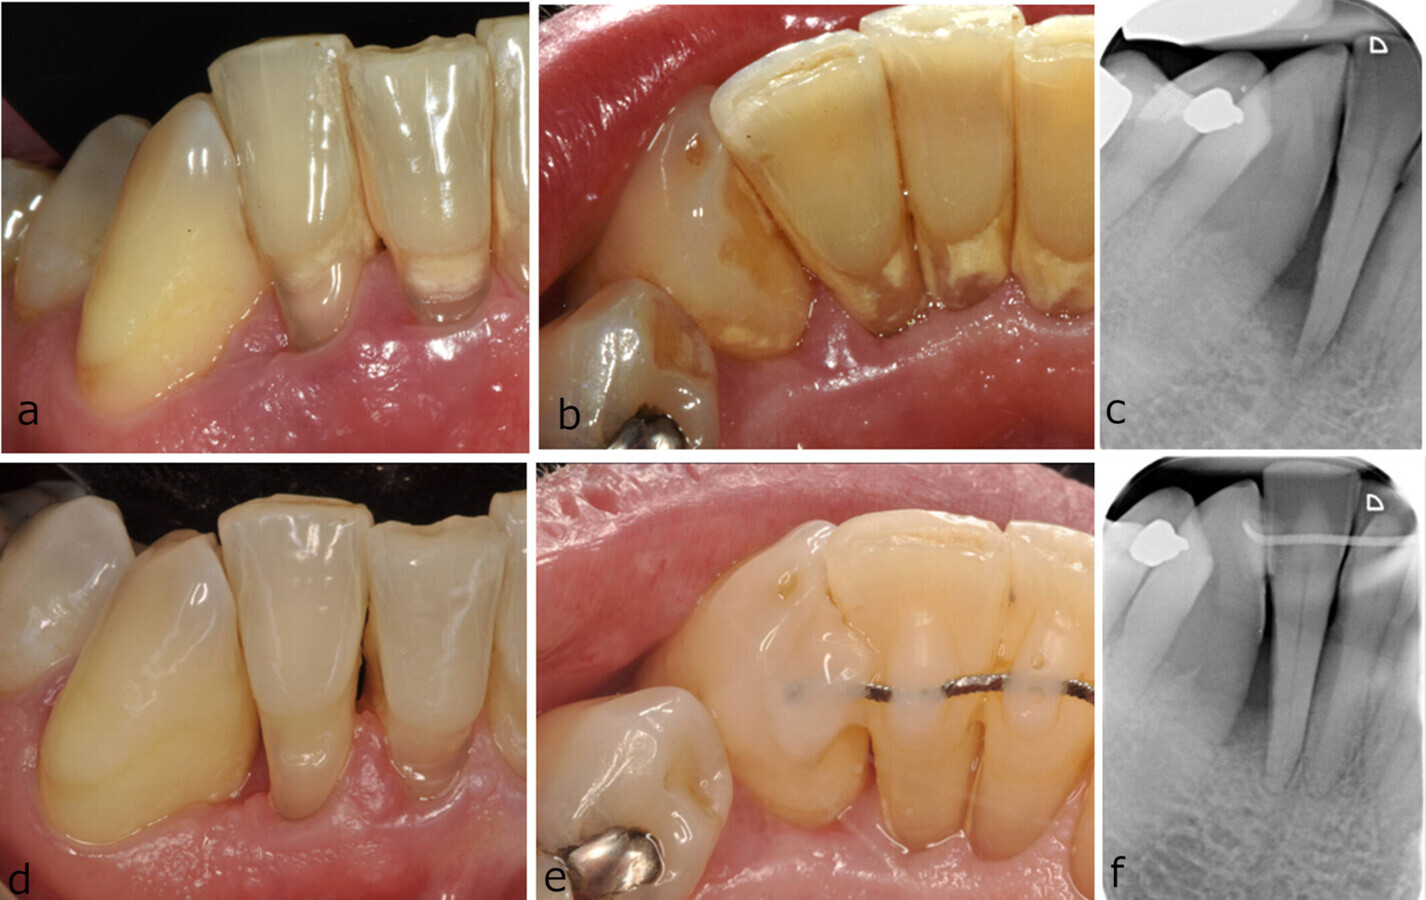

Despite its successes, regenerative surgery is associated with morbidity, complications and high material costs. Outcomes are not always predictable, and clinical failures and incomplete success have been reported. Consequently, there has been a shift towards more patient-friendly alternatives such as minimally invasive non-surgical therapy (MINST). This approach aims to minimise tissue trauma and enhance wound healing by avoiding surgical incisions and suturing. However, as the predictability, generalisability and wide applicability of MINST remain unclear, the research team’s goal was to assess the effect of MINST in intra-bony defects.

The study evaluated data on 48 patients with one or more intra-bony defects who were treated in private practice in the UK, Italy and Spain. The patients received Step 1 and Step 2 periodontal therapy, including MINST. Clinical and periapical radiographic data was analysed at the beginning of the treatment and 12 months thereafter.

The mean total radiographic defect depth was reduced by 1.42 mm, and the defect angle increased by 3°. Statistically significant improvements in probing pocket depth (PPD) and clinical attachment level (CAL) were seen at 12 months compared with baseline. A PPD of 4 mm or less was achieved for 66.7% of the defects, and 58.3% of the defects gained 3 mm in CAL in addition. Deeper and narrower-angled defects showed greater radiographic and clinical improvements, respectively.

“These findings agree with the outcomes reported in previous single-centre studies on MINST, providing additional confirmation that an atraumatic technique, which minimises tissue damage and trauma while promoting gingival margin stability and reducing chairside time, can substantially improve intra-bony defects,” stated the study authors. However, they emphasised that achieving the clinical goal of a PPD of less than 5 mm and no bleeding on probing may require surgical intervention in some cases.